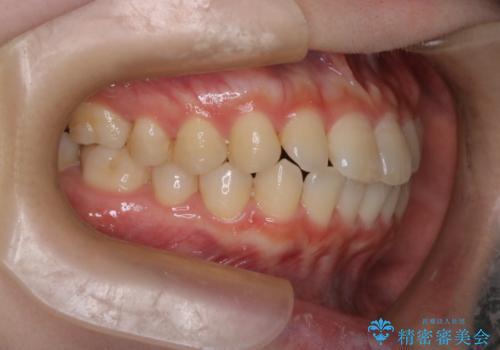

前歯と奥歯のガタガタを矯正で改善

- 患者様は、前歯と奥歯のガタガタ(叢生)を改善し、正面から見た時の歯並びを美しく整えたいとのご要望で来院されました。診断の結果、非抜歯での矯正が可能と判断し、インビザラインを使用する治療計画を立案しました。透明な矯正装置で目立ちにくい治療を行いながら、前歯と奥歯の両方を整列させることを目標にしました。

インビザラインを用いて、前歯の見た目を重視しつつ、奥歯のガタガタも改善しました。特に正面から見た際の美しい歯列を意識し、段階的に歯を移動させることで、全体の調和を図りました。治療中は、適切な装着時間を守ることや、装置の清潔を保つことが重要でした。また、歯肉や歯列全体に無理な負担がかからないように移動を管理しながら治療を進めました。結果として、前歯と奥歯がきれいに並び、見た目にも機能的にも満足いただける仕上がりとなりました。